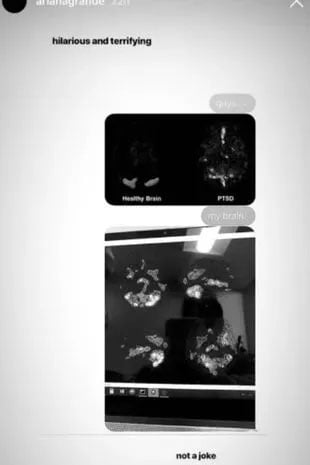

For example, Ariana shared an image of a “healthy brain” and the brain of a person with an SSPT on Instagram.

To compare them with hers, she posted her brain scanner, who looked like someone who suffered from a mental disorder.